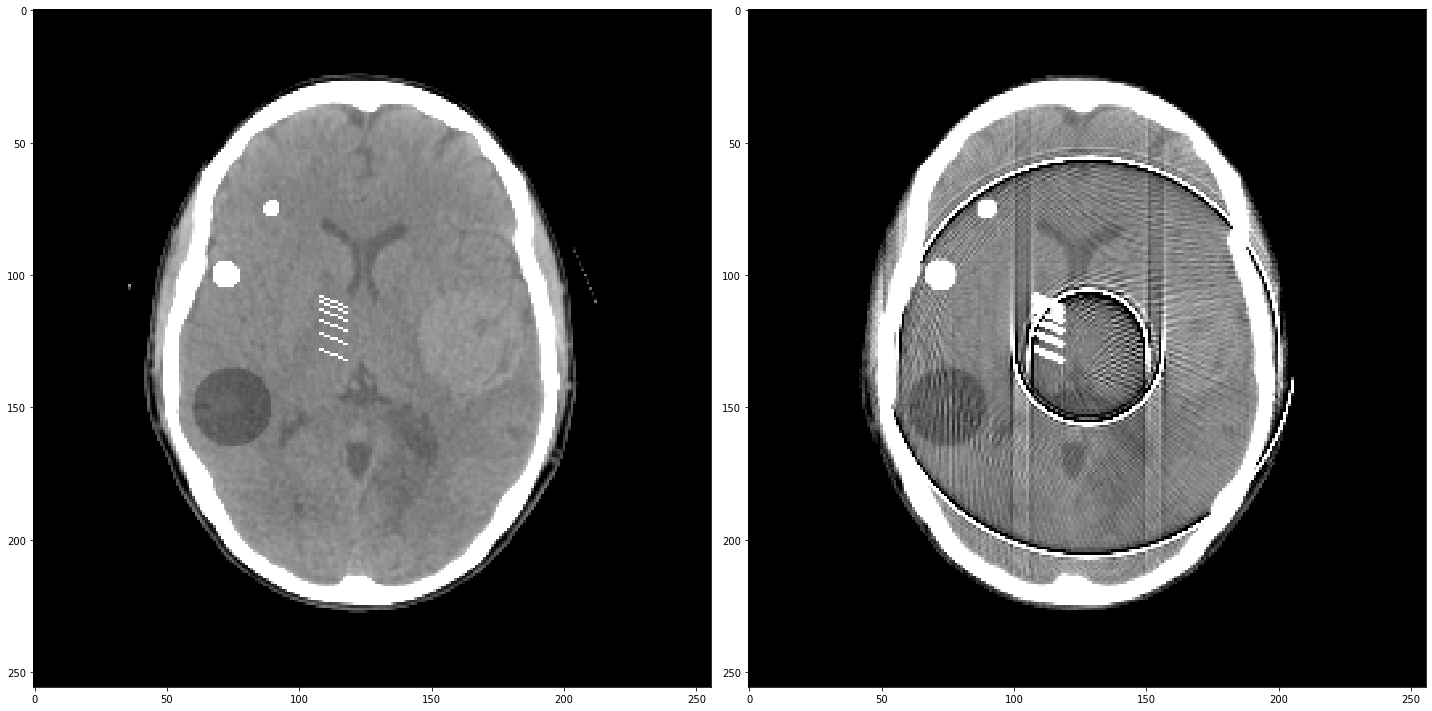

# Question 12

search = np.linspace(0,1,11)

for alpha in search:

rec = out+alpha*reproj

f,ax = plt.subplots(1,2,figsize=(12,5))

ax[0].imshow(rec,vmin=0,vmax=0.5)

ax[0].set_title(alpha)

im = ax[1].imshow(img[80]-rec)

f.colorbar(im,ax=ax[1])

ax[1].set_title('Difference from ground truth')

plt.show()